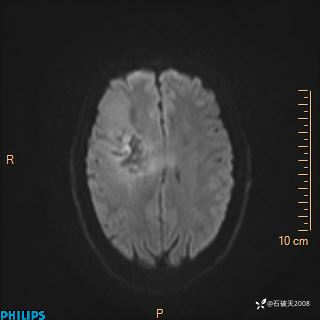

2024.2.21MR

DWI